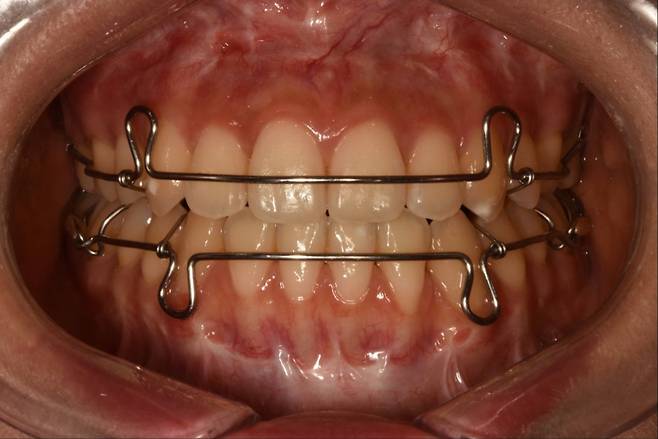

고정식 유지장치는 교정 치료를 종료하기 전 또는 직후에 얇은 철사를 앞니 안쪽에 붙이는데, 겉으로는 잘 보이지 않는다. 교정 치료를 끝낸 직후, 앞니 치아 배열은 흐트러지기 쉬워 고정식 유지장치로 치열을 유지한다.

고정식 유지장치는 치아에 붙어있어 환자가 임의로 제거할 수 없다. 처음에는 다소 이물감을 느낄 수 있지만 대개 일찍 적응해 거의 불편감을 느끼지 못하게 된다. 착용에 신경 쓸 필요가 없어 편리하지만, 구강위생 관리가 소홀할 경우 장치 주변에 음식물이 남아 치석이 생기는 경우가 있다. 특히 침이 나오는 부분과 가까운 아래 앞니 유지장치 주위에 치석이 생기는 경우가 많아, 양치질 시 꼼꼼히 닦아야 한다.

고정식 유지장치 철사는 탄성이 있고, 잘 변형되지 않아 일상에서 망가지는 경우는 거의 없지만, 지나치게 단단한 음식물을 섭취할 경우 강한 외력에 철사가 탈락하거나 변형될 수 있다. 고정식 유지장치가 부착된 부위는 치실을 일반적인 방법으로 사용하기 어렵고, 잘못 사용해 철사에 무리한 힘을 주게 되면 장치가 변형될 우려가 있다.